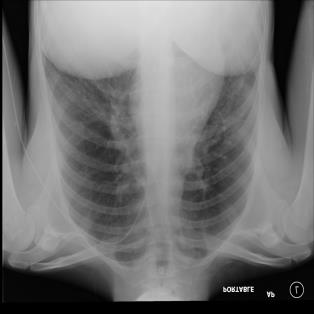

The COVID-19 disease was first discovered in Wuhan, China, and spread quickly worldwide. After the COVID-19 pandemic, many researchers have begun to identify a way to diagnose the COVID-19 using chest X-ray images. The early diagnosis of this disease can significantly impact the treatment process. In this article, we propose a new technique that is faster and more accurate than the other methods reported in the literature. The proposed method uses a combination of DenseNet169 and MobileNet Deep Neural Networks to extract the features of the patient's X-ray images. Using the univariate feature selection algorithm, we refined the features for the most important ones. Then we applied the selected features as input to the LightGBM (Light Gradient Boosting Machine) algorithm for classification. To assess the effectiveness of the proposed method, the ChestX-ray8 dataset, which includes 1125 X-ray images of the patient's chest, was used. The proposed method achieved 98.54% and 91.11% accuracies in the two-class (COVID-19, Healthy) and multi-class (COVID-19, Healthy, Pneumonia) classification problems, respectively. It is worth mentioning that we have used Gradient-weighted Class Activation Mapping (Grad-CAM) for further analysis.